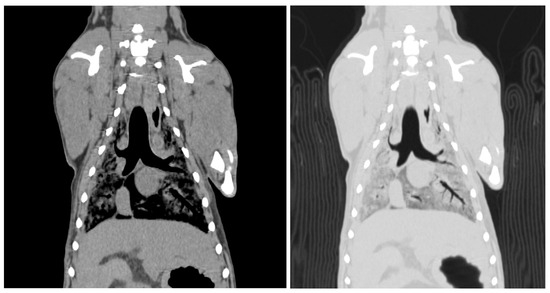

Two readers assessed the image quality of the CT scans. The visibility of the skull and lateral ventricle of the cerebrum in the head region was rated. The visibility of the thoracic structures, including the lung parenchyma, heart, aorta, cranial vena cava, and vertebrae, was scored (Figure 3). The visibility of the aorta, caudal vena cava, liver, kidney, spleen, and vertebrae was assessed.

Figure 3.

Computed tomographic image of the thorax of an SS cadaver 12 weeks after embalming. These images were reconstructed with soft tissue and a lung window. The mean score is 2.50. Lung parenchyma = 1, heart = 3, thoracic aorta = 3, cranial vena cava = 2.5, thoracic vertebra = 3. The scores were assigned as follows; 0 = not visible, 1 = poorly visible, 2 = adequately reproduced, 3 = excellent reproduced.